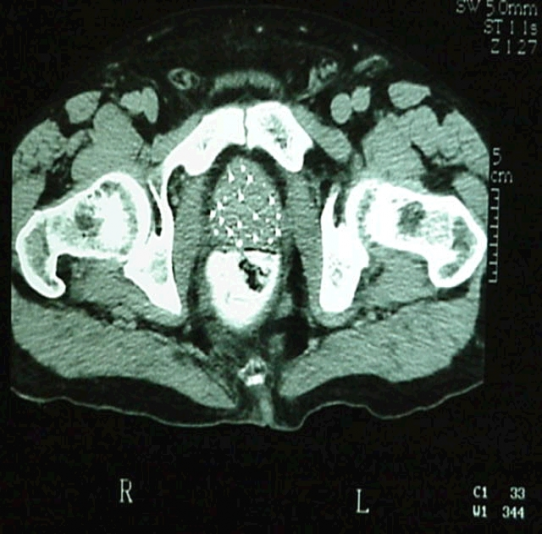

EM UMA CONSULTA UROLÓGICA DE ROTINA COM HISTÓRIA CLÍNICA COMPLETA, EXAME DE TOQUE RETAL (IMPRESCINDÍVEL), EXAMES DE IMAGEM COMO ULTRASOM E DOSAGEM SANGUÍNEA DE PSA SÃO OBRIGATÓRIOS E DÃO FORTES SUBSÍDIOS PARA DIAGNÓSTICO DAS DOENÇAS PROSTÁTICAS, TANTO BENÍGNAS COMO MALÍGNAS.